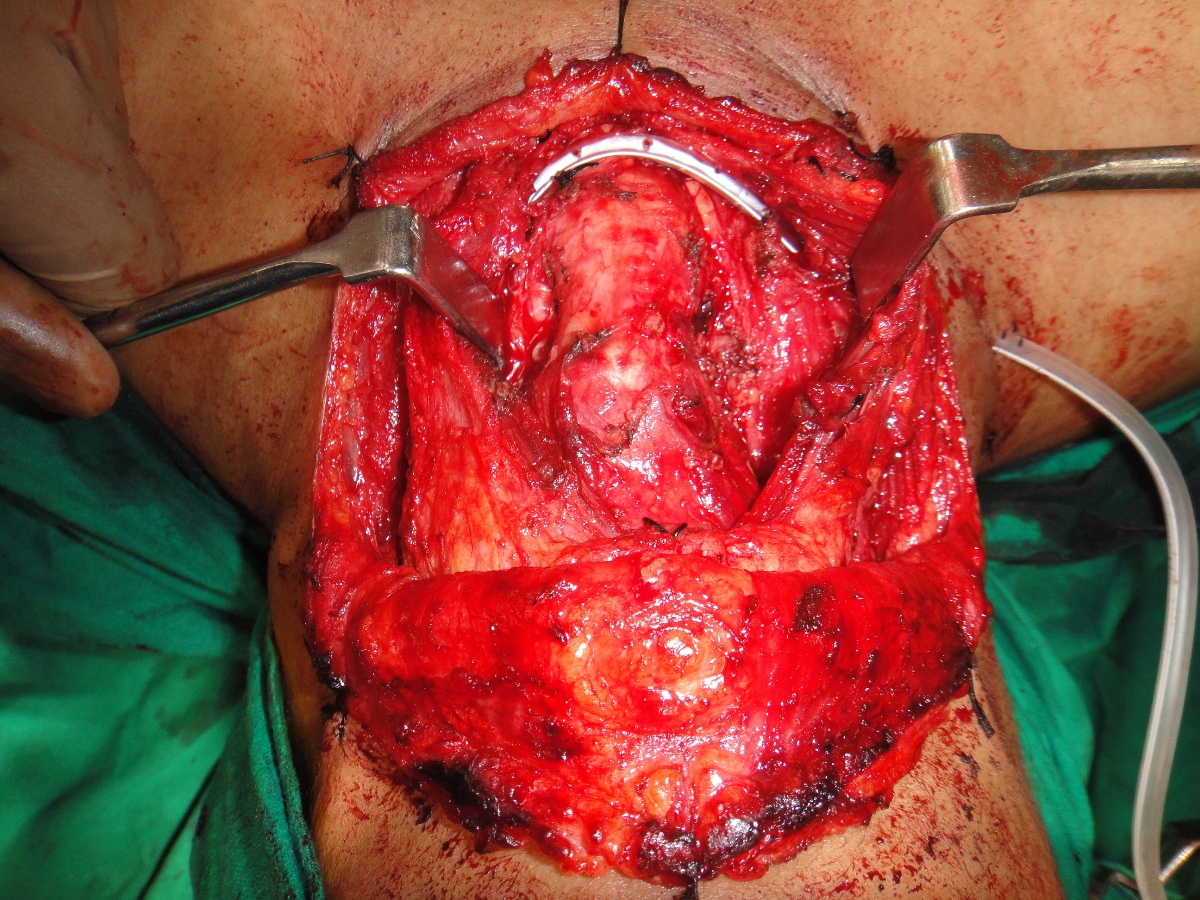

75 yrs old patient having right upper alveolus carcinoma.patient was operated for right buccal mucosa carcinoma in 2009.pet ct shows localised disease with minimal uptake in left neck node.Right subtotal maxillectomy done with Right PM flape.